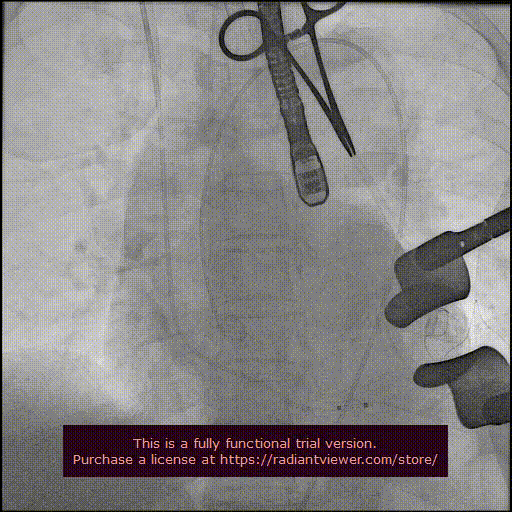

造影显示主动脉窦部

从心尖置入输送系统

定位件入窦

瓣膜降至瓣环平面

释放瓣膜

造影确认瓣膜位置

撤出输送系统

造影确认植入效果